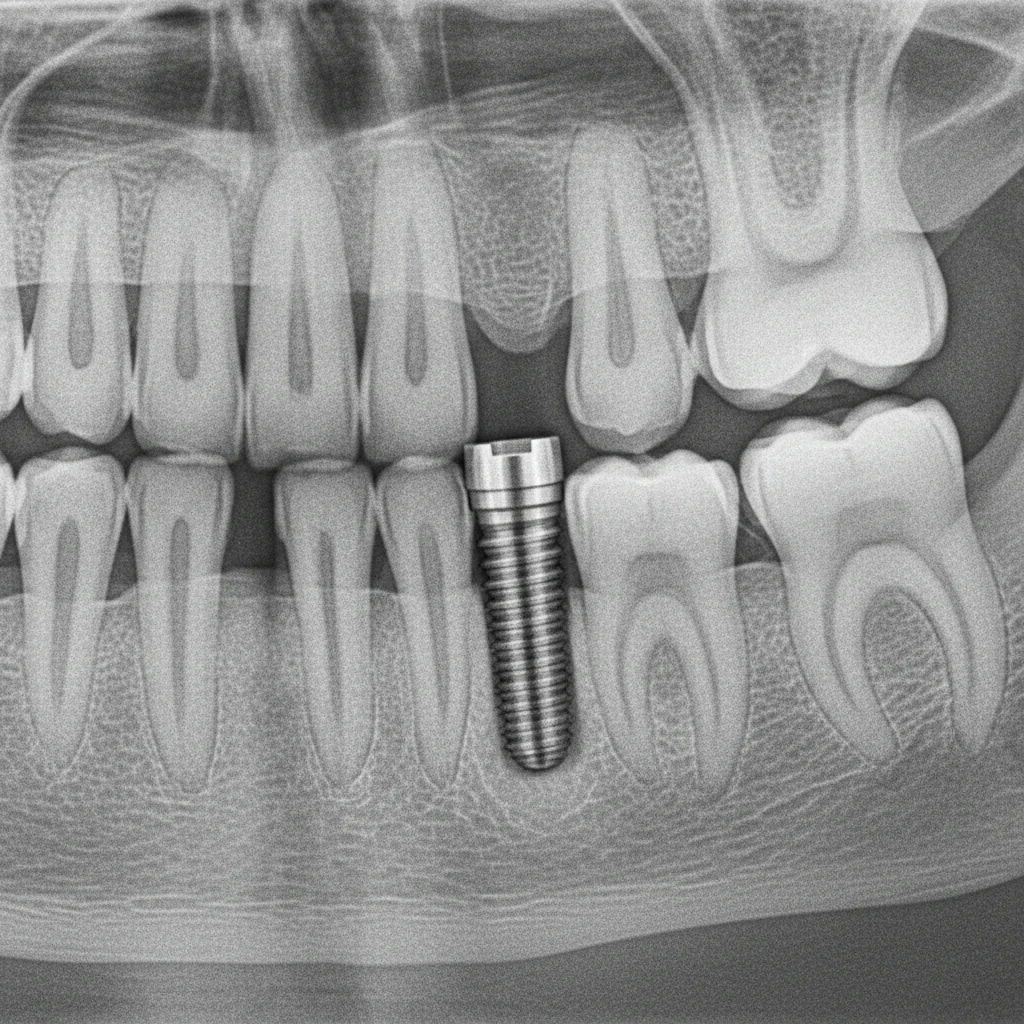

• تأیید پزشک در معاینات دوره‌ای و تصاویر رادیوگرافی

پس از گذشت سه تا شش ماه، که معمولاً زمان تکمیل اسئواینتگریشن است، ایمپلنت باید کاملاً پایدار باشد. در این زمان، دندانپزشک با معاینه بالینی و بررسی تصاویر رادیولوژی، جوش خوردن موفق ایمپلنت را تأیید کرده و مراحل نهایی درمان مانند نصب روکش انجام می‌شود.